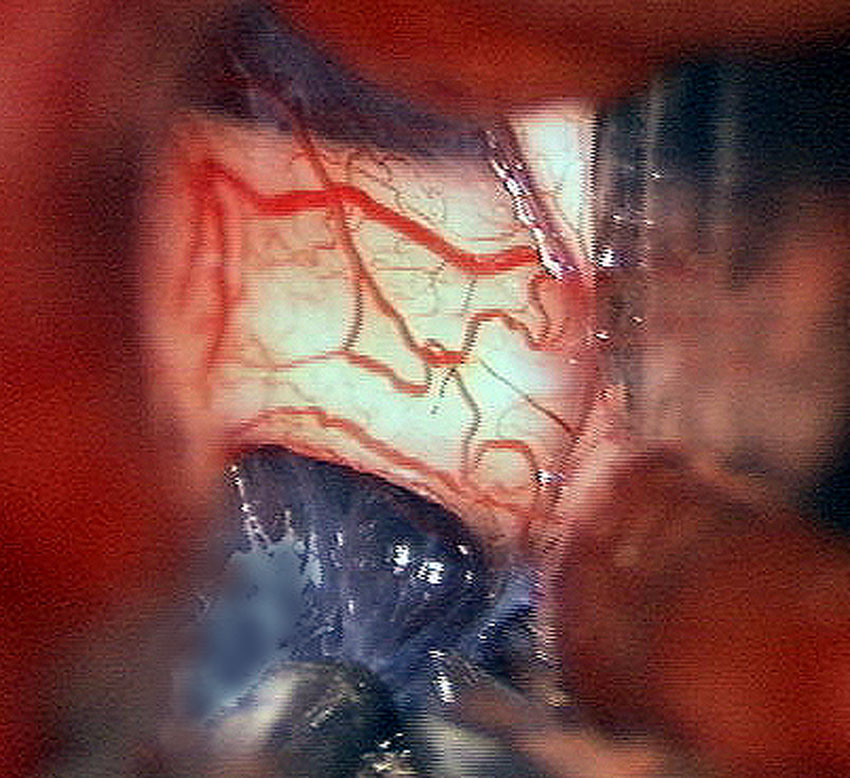

1歳児の左眼窩内単視神経膠腫です。左目は手動弁程度ですから,全摘出しました。まぶたの動きと眼球運動は温存しました。この例に何年も化学療法を続けるのは馬鹿げています。

左の写真は,左眼窩内腫瘍,右の写真は,頭蓋内の正常左視神経です。